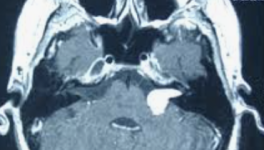

Tumeur nerveuse bénigne développée aux dépens du nerf acoustique, encore appelée schwannome, car elle naît précisément des cellules de la gaine du nerf, les cellules de Schwann.